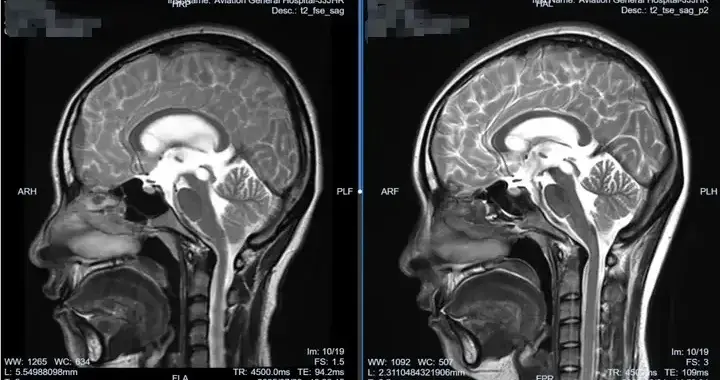

跨国生命接力!软性神经内镜成功救治蒙古国脑积水少年!